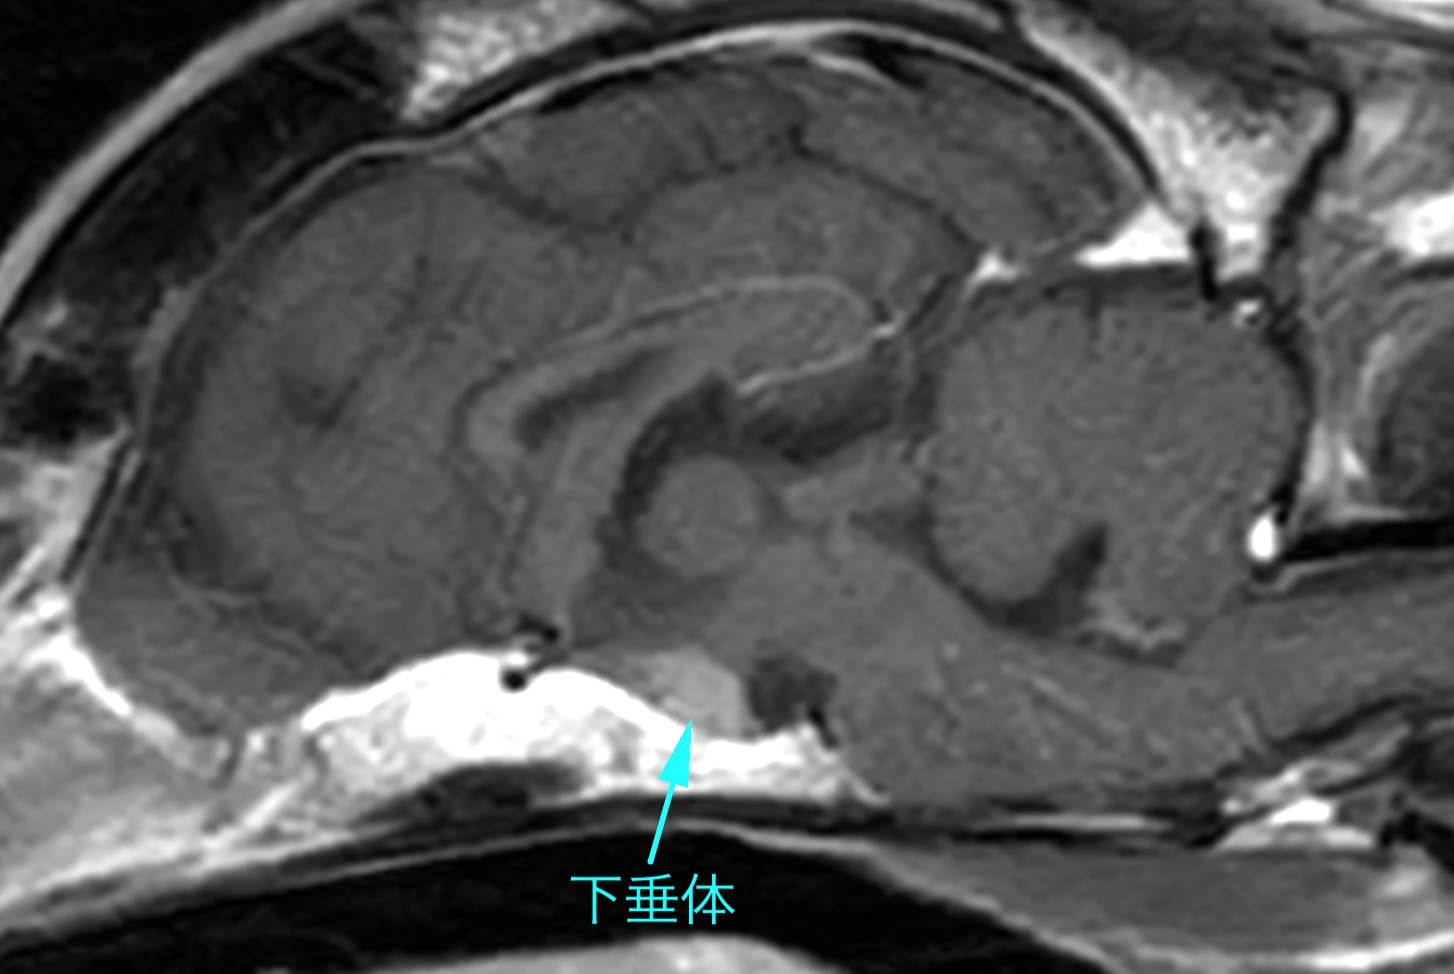

動画の子(11歳のジャックラッセルテリア)は、約2年前からこの病気が発症し、緩やかに症状が進行してきていたため当院に診断精査を希望され来院されました。MRI検査で脳・頚髄と頚部筋肉に明らかな異常所見は認められず、脳脊髄液検査にも異常は認められませんでした。以前から副腎皮質機能亢進症を患っていたことから、「副腎皮質機能亢進症を原因とした偽性ミオトニア」を疑い、筋電図検査を行ったところ、静止状態にも関わらず規則的な放電を示す"複合反復放電"が複数の筋肉で検出されたため、確定診断としました。

頭部MRI検査で脳下垂体の明らかな腫大は認められず、腹部超音波検査で副腎腫瘍を疑う所見がなかったことから、副腎皮質機能亢進症に対する一般的な内科治療を開始しました。その後、筋緊張を和らげる効果を期待した内服薬の投与も開始しています。

なお、副腎皮質機能亢進症の内服治療を開始する前にMRIで下垂体のサイズを見ておく事で、ネルソン様症候群発症のリスクを評価でき、より安全に治療が可能です。

頭部MRI 明らかな下垂体の腫大は認められず